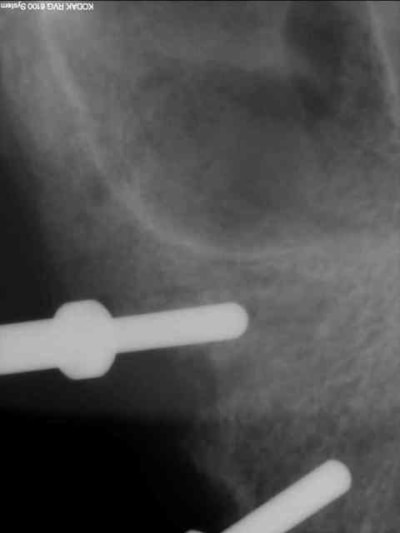

longer les parois antérieures des sinus à l'aveugle même après avoir étudié le scan...tu as fais des contrôles radios durant la phase de forage?

> longer les parois antérieurs des sinus à l'aveugle même après avoir étudié le

> scan...tu as fais des contrôles radios durant la phase de forage?

oui, c'est exactement ça .

d'abord un petit forage puis inclinaison et forage final.

je reconnais qu'il y a là une part de chance, je ne suis pas superman non plus.